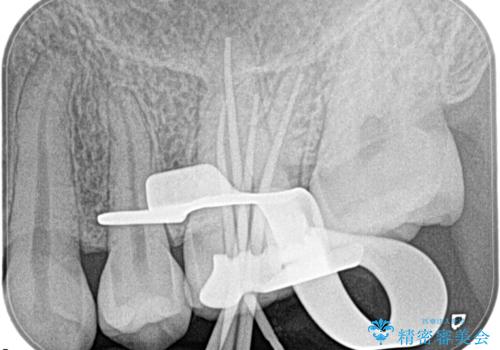

- 奥歯がズキズキ痛いことを主訴に来院されました。

検査の結果、診断を症候性不可逆性歯髄炎、症候性根尖性歯周炎とし抜髄を行っております。

主訴である痛みを解決することができました。無菌的治療を行うことで、根尖性歯周炎の予防にも期待できる治療を行いました。